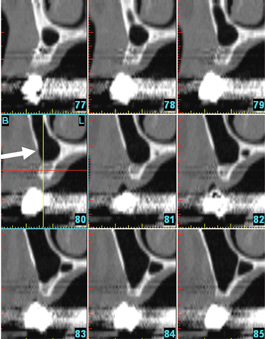

Fig 6. No anterior loop of the mental foramen: nine consecutive cross-sectional views. Sections anterior to the mental foramen do not demonstrate any radiolucency that corresponds to the loop of the inferior alveolar nerve. Arrow is pointing to the bone anterior to the mental foramen, which does not demonstrate a loop.

Figure 6